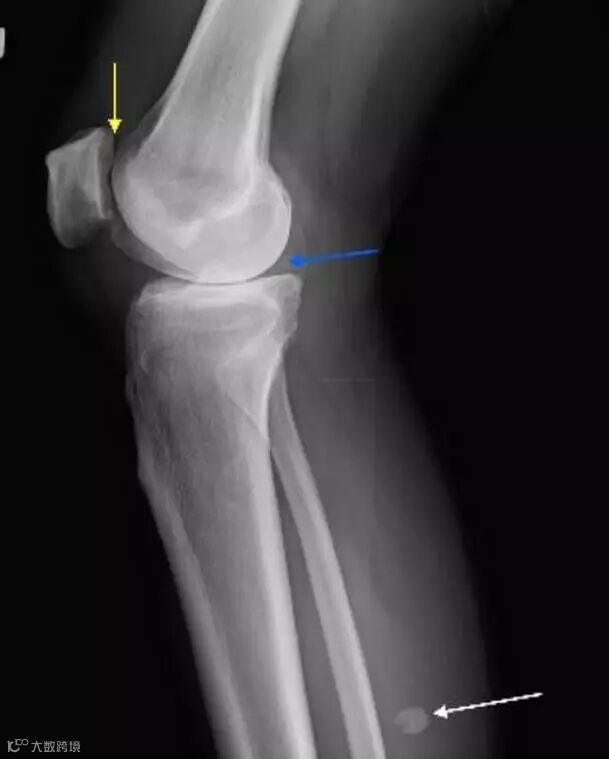

Lateral view of the left knee demonstrates joint-space narrowing (yellow arrow) and chondrocalcinosis (blue arrow). There is a calcified body (white arrow) within the inferior recess of a dissecting Baker cyst.